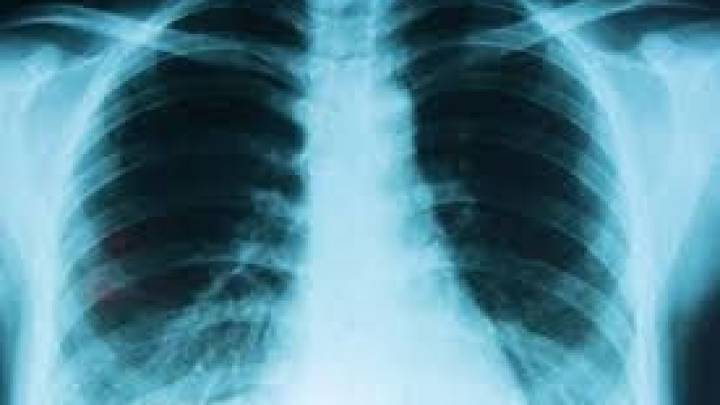

En el marco del Día Mundial del Cáncer de Pulmón, que se conmemora este lunes, los especialistas advirtieron que esta enfermedad sigue siendo una de las principales causas de muerte en el mundo, ya que, según la Organización Mundial de la Salud (OMS), provoca entre 1,8 y 2,2 millones de muertes por año, lo que equivale al 20% de todos los fallecimientos por cáncer.

Los datos para Argentina se tornan sumamente preocupantes, dado que ocupa el segundo lugar en incidencia y el primero en mortalidad oncológica : se registran cerca de 12.000 nuevos diagnósticos y alrededor de 10.000 muertes anuales , lo que representa el 15% de todos los fallecimientos por cáncer.